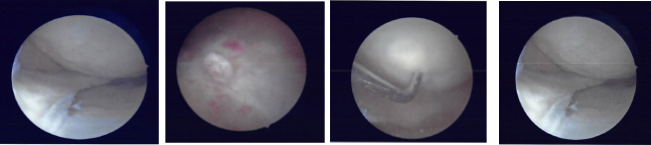

Preop antibiotic was given. Esmarch was used to exsanguinate the limb and tourniquet was elevated to 300 mmHg. Lateral entry portal was made and an arthroscope was introduced into the knee joint. There was no osteochondral lesion of the patellofemoral joint, medial condyle, lateral condyle.

Examination of the medial meniscus showed a big body oblique vertical tear of the medial meniscus along with tear of the posterior horn of the medial meniscus. There was ACL tear, which was not repairable due to edgy mid-substance.

There was a lateral meniscus tear along the mid substance and anterior body of the lateral meniscus, which was flipped inside. Medial entry portal was made. Probe was introduced and the lateral meniscus tear was reduced with difficulty.

The lateral meniscus tear was held in place using a spinal needle, through which a Fiber Wire was passed. The FiberWire was used as a holding suture. Meniscal stitch from Arthrex were used x2 to repair the lateral meniscus.

Similarly, the medial meniscus was also reduced and sutured using two meniscal stitches from Arthrex. Fast-Fix chrome from Smith & Nephew was used for repair of the meniscal of the posterior horn. The repairs were satisfactory. Pictures were taken and saved.

Intraoperative Arthroscopic Images